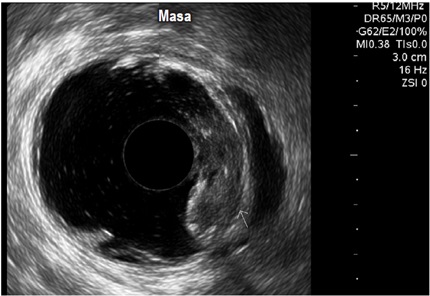

Por otro lado, en el grupo masculino con estudio por incontinencia, el diagnóstico en todos fue cambios por atrofia del aparato esfinteriano, que pudo verse en cualquiera de las localizaciones del canal anal y que se evidenció como engrosamiento de los músculos en general y cambios difusos de la ecogenicidad de los mismos, sin posibilidad de determinar el borde que los delimita. Se encontró fístula perianal en 16 pacientes (11,8%); la principal forma de presentación de las fístulas fue transesfintérica (37,5%), seguida por las interesfintéricas y anovaginales (figuras 3 y 4). Doce pacientes presentaron absceso perianal (8,8%); de estos, el 83% correspondió a abscesos submucosos o isquiorrectales (figura 5).

Los demás diagnósticos finales se presentan en la tabla 4. Es de resaltar que se pudo determinar en el grupo diagnosticado como neoplasia benigna de recto, la posibilidad de resección endoscópica en lesiones que tenían planeadas cirugías más invasivas (figura 6 y 7), así como la posibilidad de determinar la recuperación del aparato esfinteriano en 3 pacientes en seguimiento por cáncer de canal anal después de manejo por parte de oncología. En 2 pacientes de los diagnosticados con neoplasia maligna de recto se identificó lesión menor a T2 y N0 según las clasificación de TNM (figura 8), considerándose lesiones tempranas; en el otro 88,8% se encontraron lesiones avanzadas (figura 9 y 10). También se anota que, dentro de la categoría otros, están con orden de frecuencia de mayor a menor endometriosis o endometrioma, enterocele, fisura anal, várices rectales y un caso de cáncer de colon sigmoides.

De igual forma, la importante frecuencia de indicación en pacientes con neoplasia maligna rectal confirmada habla de la aceptación a nivel nacional y regional que se le está dando a este diagnóstico por parte de grupos interdisciplinarios de oncología, donde la endosonografía juega un papel fundamental a la hora de complementar otras ayudas diagnósticas para estadificación locorregional y planeamiento adecuado de la terapia (4, 9, 19, 20, 21, 22).